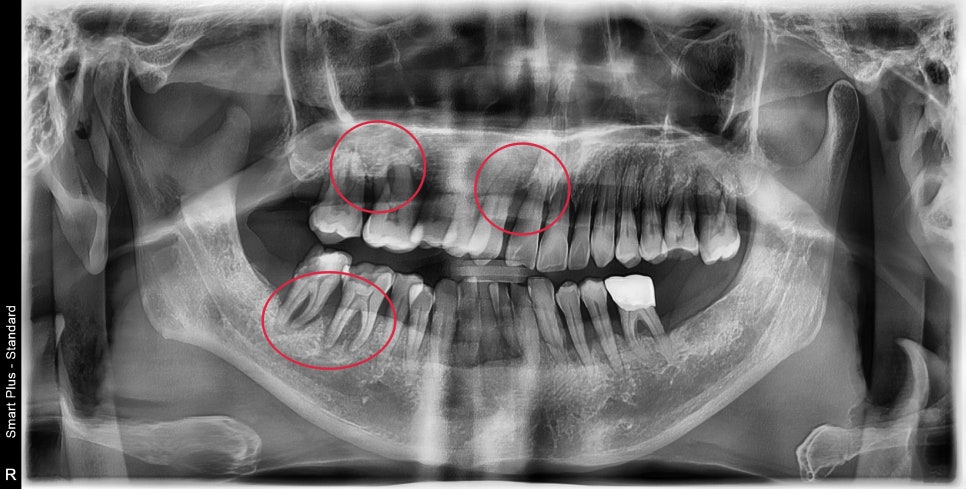

초진 사진입니다.

빨간색 원으로 표시된 부분이 특히 뼈가 많이 녹아 많이 흔들렸으며

나머지 치아들도 전반적으로 동요도가 있었습니다.